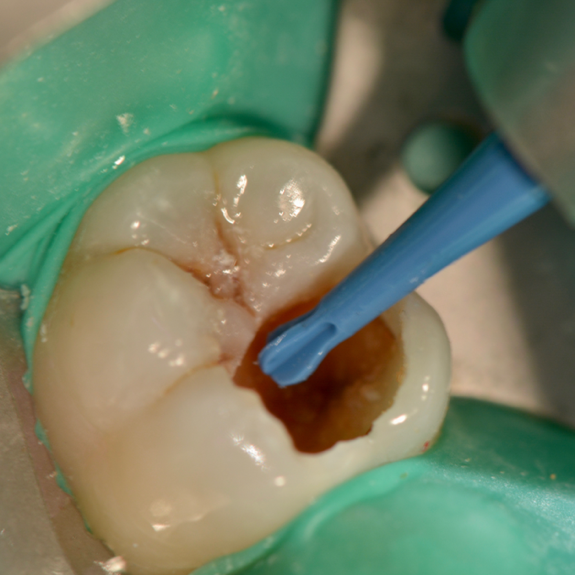

Clinical steps for occlusal caries group (BCD group) (A,K Caries Excavation Meaning  Preoperative clinical photo and radiograph (red circle); Clinical steps for occlusal caries group (bcd group): Two randomized controlled trials comparing stepwise and complete excavation, while only tangentially relevant to the partial. The aim of this article is to review the scientific evidence for deep caries removal in permanent vital teeth and the choice. Since the invention and application of rotary. Caries Excavation Meaning.